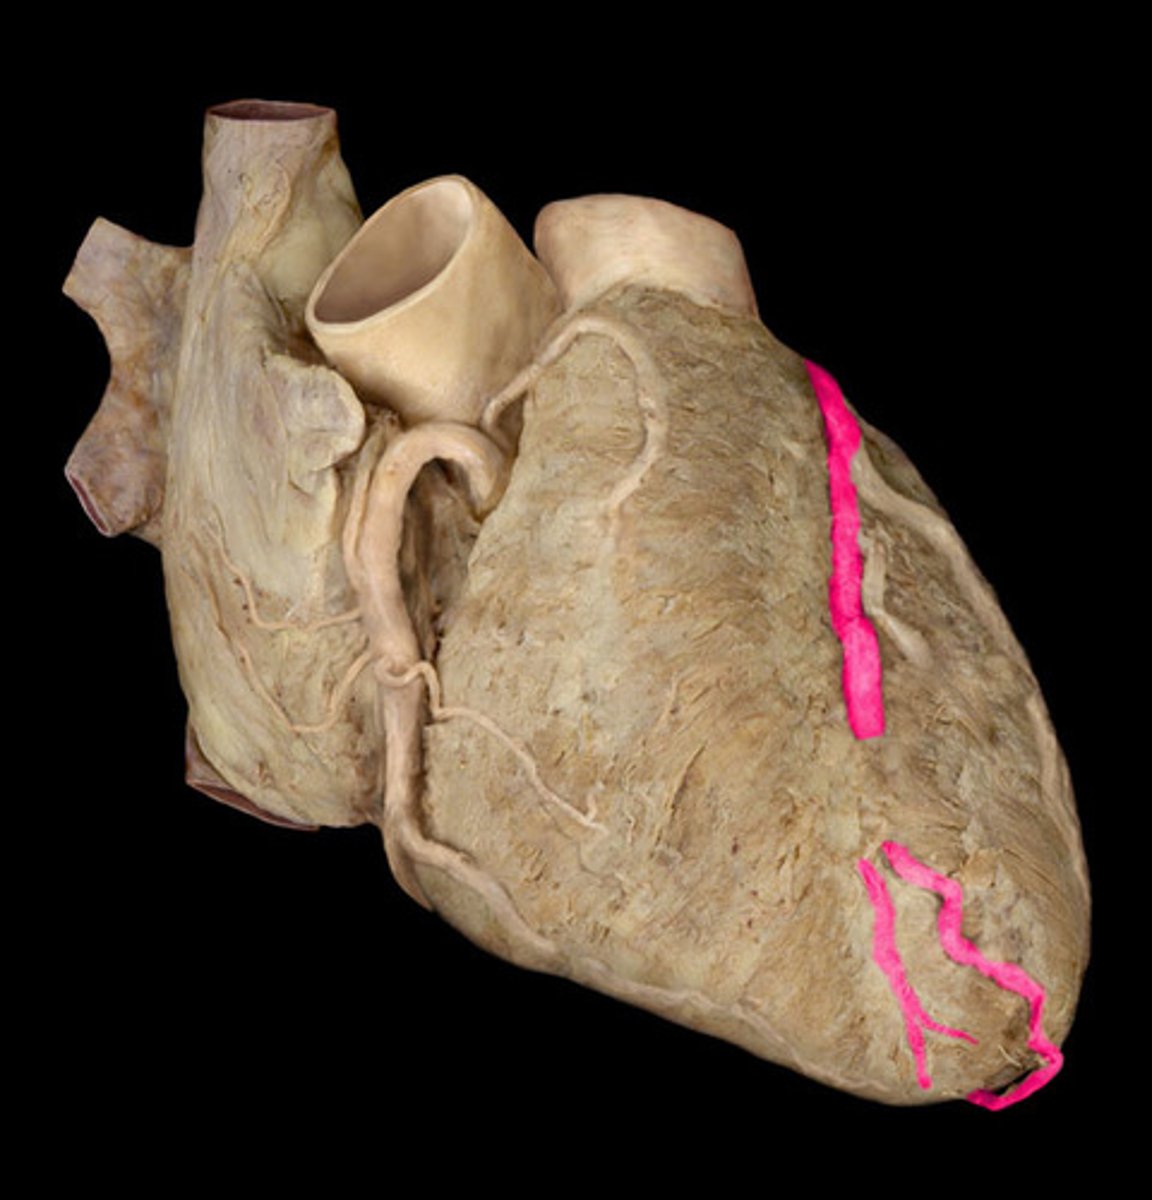

anterior interventricular sulcus

the junction between right and left ventricles

anterior side (depression)

anterior interventricular artery

in the anterior interventricular sulcus

great cardiac vein

begins in the anterior interventricular sulcus

left side of the 'T'